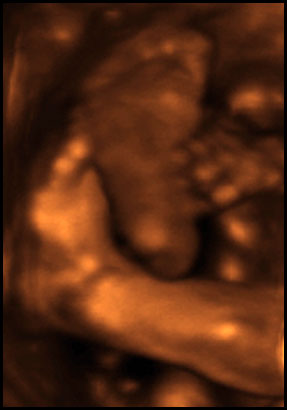

The whole process was very cool, the baby was super active and we saw him making lots of faces and playing with the umbilical cord (note to unborn child: stop gnawing on your life support system). We were also shown a closeup of what I shall refer to as the Twig And Berries, which I will carefully archive in order to humiliate him in the future - on, say, prom night.

So, how about some pictures?

First, some notes on what you're seeing, in case some of these graphics seem a little weird. The machine only captures 3D images in a small area, and anything outside the area is either not visible or appears as blurriness. Also, while the technician tried for a good face shot, the baby's head was partially smooshed against the placenta the whole time, so it was never possible to get a really clear eyes/nose/mouth image.